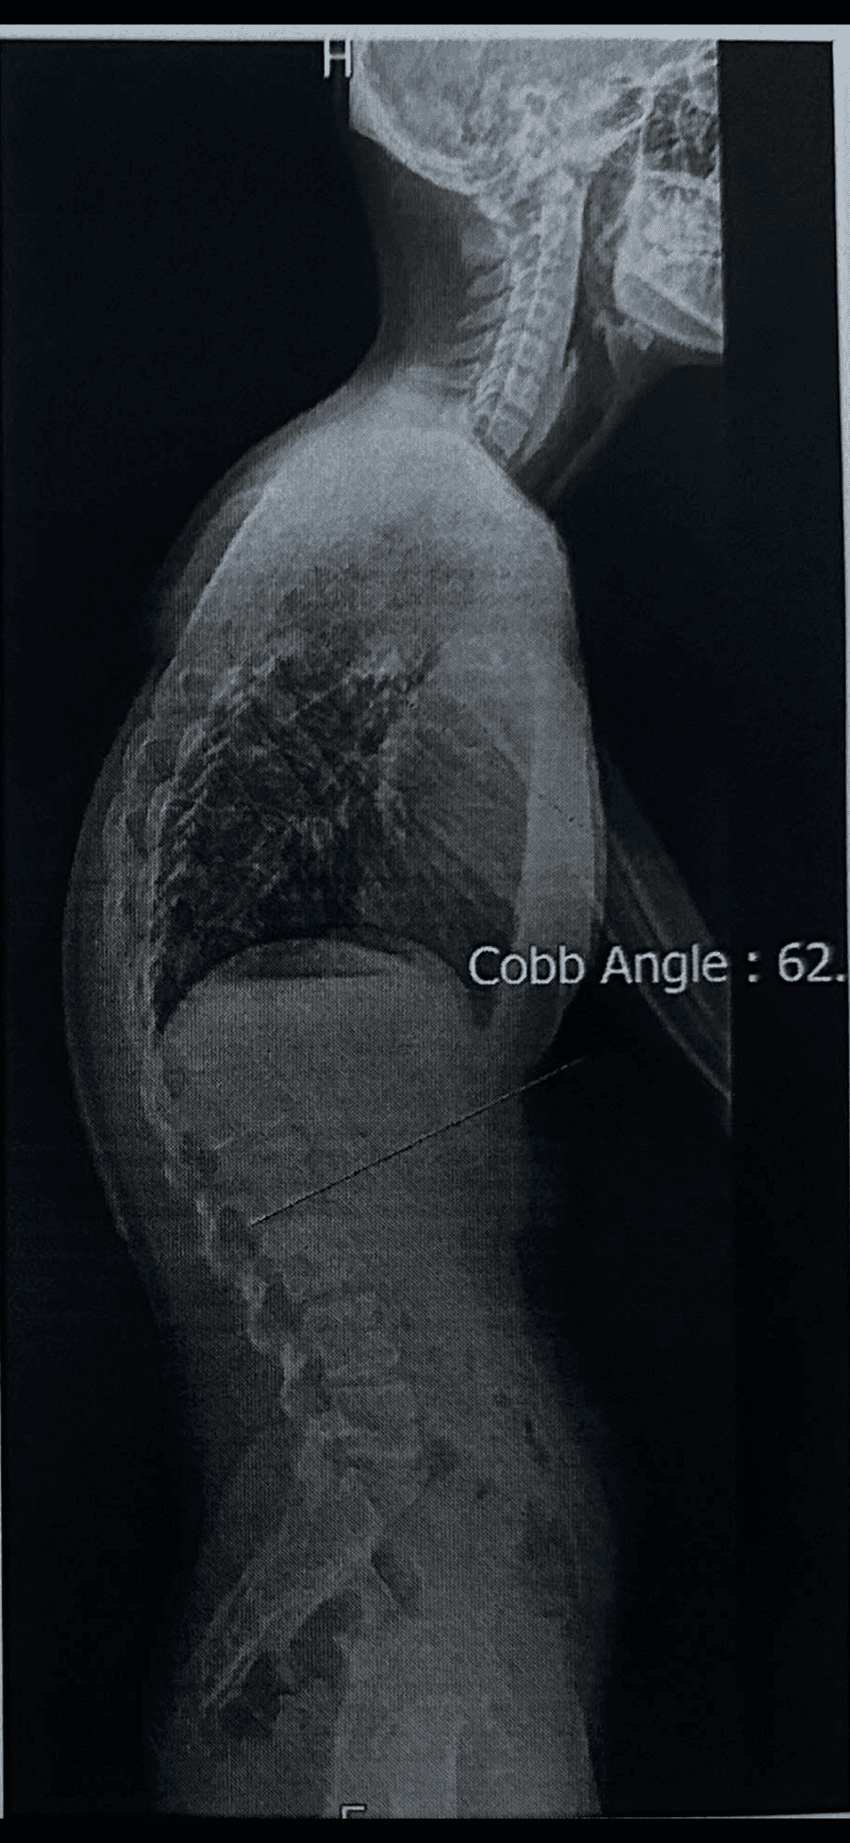

측만증이랑 다른건가... 받는 수술은 비슷하네. 저거 별거 아닌 것 같아도 저승문 터치하고 오는거 맞지..